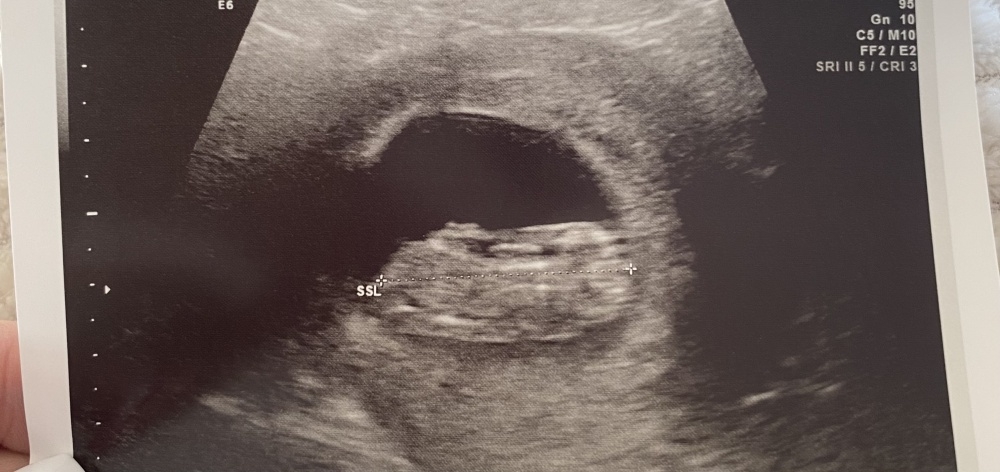

Kennt sich hier eventuell jemand mit der Nub Theorie aus & könnte seinen Tipp abgeben?

Bin aktuell in der 11. SSW & das Bild ist von Gestern.

ihr Lieben was würdet ihr bei mir sagen Mädchen oder Junge. Bild ist von der 12+2.